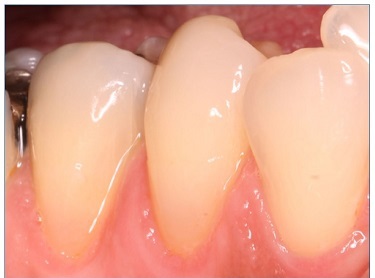

There were no dropouts in this study, so all patients were evaluated at baseline and at 6 months. Representative images of restorations are presented in Figures 1, 2, 3, 4, 5, and 6.

Figure 2 Photographs after 6 months of tooth 34’s restoration by the etch‑and‑rinse technique and tooth 45’s restoration by the self‑etch technique